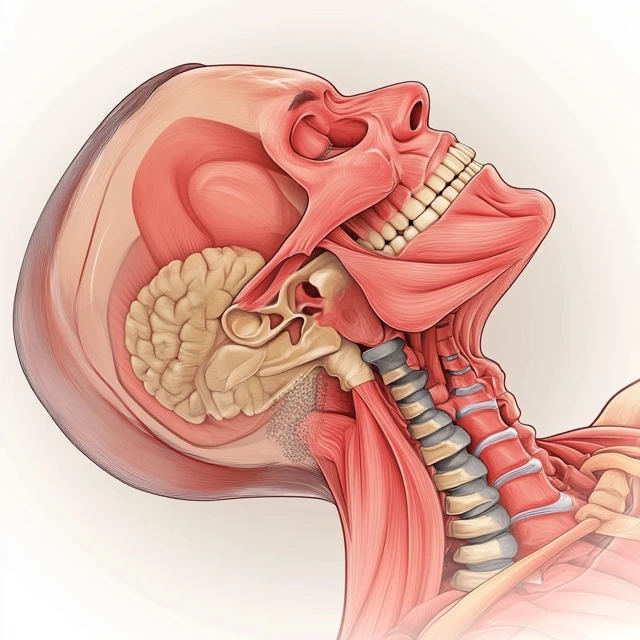

목디스크의 증상은 일반적으로 몇 가지 초기 신호로 나타납니다. 이를 조기에 인지하고 대처하는 것이 매우 중요합니다. 특히 다음과 같은 증상이 나타난다면, 즉시 전문가의 진료를 받는 것이 좋습니다. 목디스크는 주로 목의 디스크가 찢어지거나 탈출되면서 발생하는데, 이로 인해 주변 신경이나 척수에 압박이 가해지는 경우가 많습니다. 주요 초기 신호는 다음과 같습니다:

- 목의 통증: 목디스크의 가장 일반적인 초기 증상은 목의 통증입니다. 이 통증은 지속적일 수도 있고, 특정 자세를 취할 때 더욱 심해질 수 있습니다. 일반적인 근육통과는 다르게, 목의 통증은 종종 뻣뻣함과 함께 오는 경우가 많습니다.

- 어깨와 팔의 방사통: 목디스크로 인한 신경 압박으로 인해 어깨나 팔로 방사되는 통증을 느낄 수 있습니다. 이러한 방사통은 날카롭거나 찌릿한 느낌이 들며, 특히 팔을 움직일 때 그 강도가 증가할 수 있습니다.

- 감각 이상: 목디스크는 신경을 소프트하게 압박하기 때문에 팔이나 손에서 감각 이상이 나타날 수 있습니다. 예를 들어 지속적인 저림이나 무감각 현상이 발생할 수 있습니다.

- 근력 약화: 목디스크가 심각해지면 팔이나 손의 근력이 약해질 수 있습니다. 이는 일상생활에서 물건을 쉽게 들기가 어렵거나, 손가락의 힘이 줄어드는 것을 의미합니다.

- 머리의 통증: 목디스크의 통증은 두통으로도 이어질 수 있습니다. 특히 긴장성 두통과 비슷한 유형의 두통이 발생할 수 있으며, 이는 경추가 제대로 기능하지 못할 때 나타납니다.